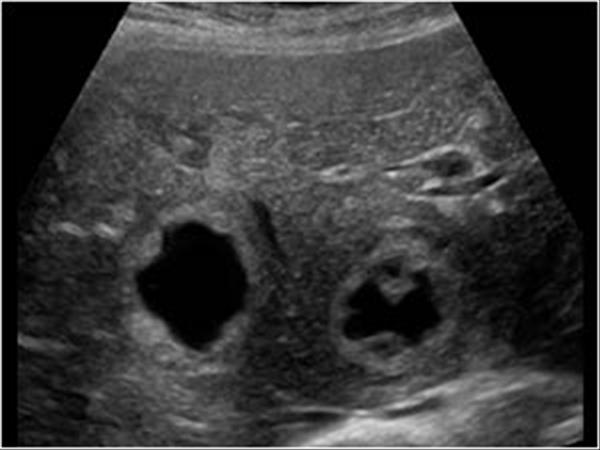

Polycystic Liver